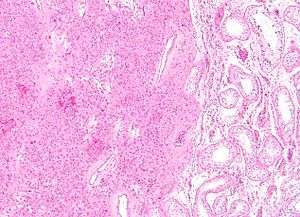

Intermediate magnification micrograph of a Leydig cell tumour. H&E stain.

High magnification micrograph of a Leydig cell tumour. H&E stain.